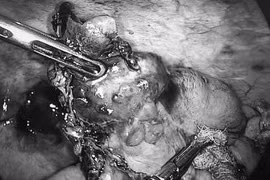

Cứu sống người phụ nữ bị u xơ tử cung biến chứng hiếm gặp

Bệnh viện Sản Nhi tỉnh Ninh Bình vừa phẫu thuật cấp cứu thành công cho bệnh nhân bị u xơ tử cung dưới thanh mạc xoắn, biến chứng hiếm gặp.